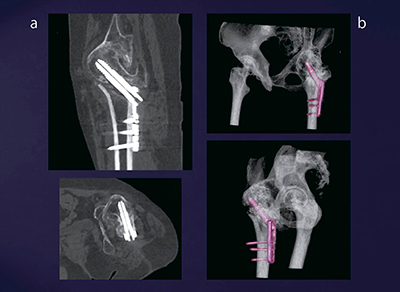

症例1は,60歳代,女性,大腿骨頸部骨折。かなり厚い金属プレートで骨折部位が固定されているが,その骨癒合の状態の評価のためにDual Energy CTが施行された。撮影パラメータを図3に示す。monoenergetic image(図4a)では,金属アーチファクトが大幅に軽減した画像が得られ,自動作成される3D画像(図4b)と併せて診断可能である。

図5は,syngo.viaで表示されるmonoenergetic imageである。実際には1keVごとに表示されるため,その中から最も評価しやすい画像を選択する。患者がリハビリに移行するタイミングの評価などにきわめて有用である。

図4 症例1:monoenergetic image(a)とその3D画像(b)